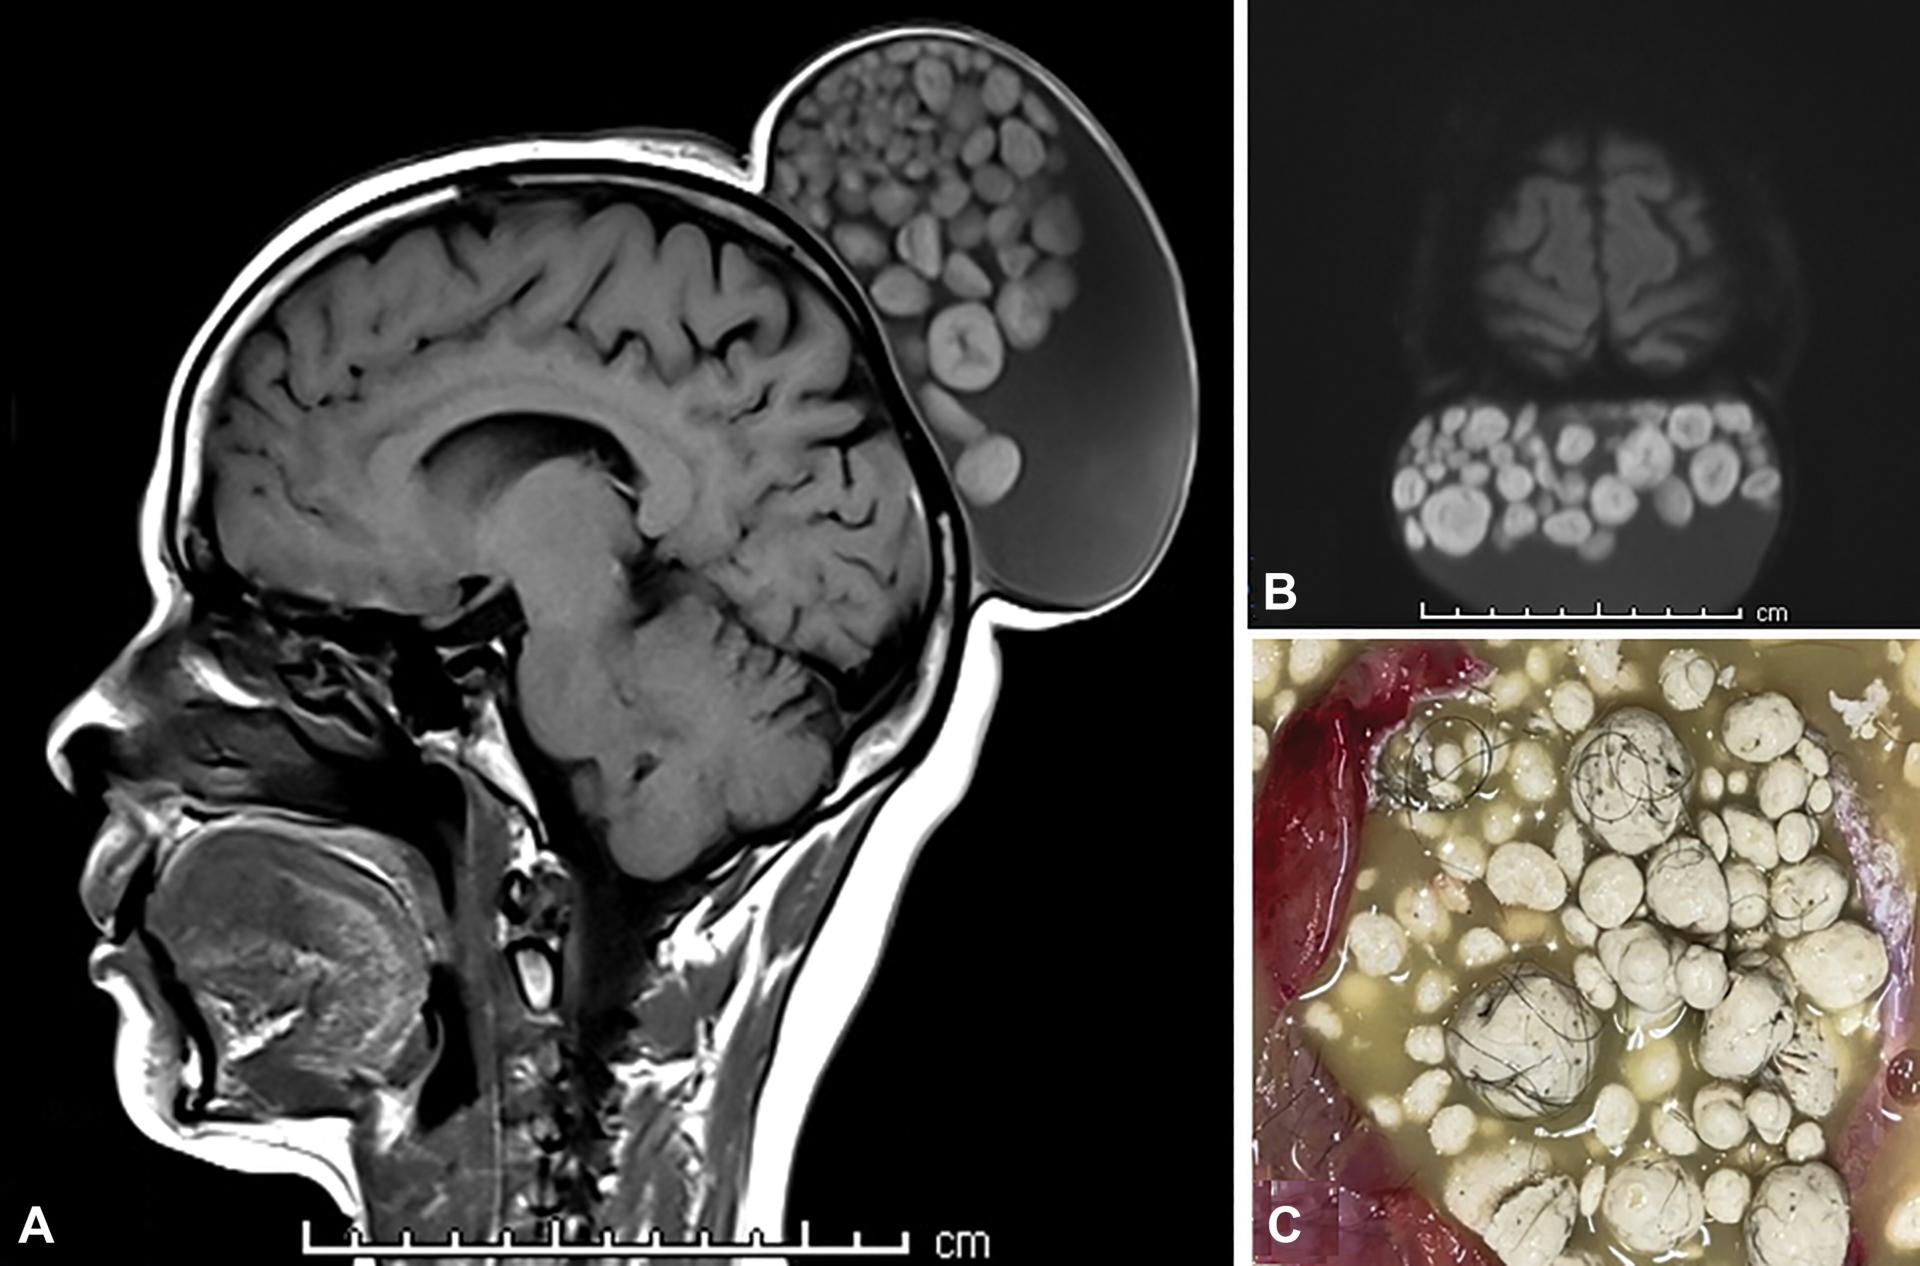

52-letnia kobieta zgłosiła się do lekarza z bezbolesnym guzem, który od czasu dzieciństwa pacjentki przez lata powiększał swój rozmiar. Badanie ujawniło, że ma on wymiary 15x10x12 cm. Wykonane badanie obrazowe MRI ujawniło dużą torbielowatą zmianę w płaszczyźnie podgałkowej skóry głowy, którą autorzy pracy porównali do "worka kulek". W opublikowanym na łamach "Radiology" obrazie MRI rzeczywiście widoczna jest okrągła torbiel wypełniona guzkami przypominającymi małe kulki.

"Po zakończeniu chirurgicznego wycięcia stwierdzono, że torbiel zawiera materiał przypominający sebum, twarde kuleczki i liczne kosmyki włosów" – piszą autorzy.

Badanie histopatologicznie na podstawie pobranych po resekcji guza próbek ujawniło, że pacjentka miała dojrzałego potworniaka torbielowatego. Po miesiącach obserwacji, jak wskazują autorzy publikacji, guz nie wykazywał tendencji do nawrotu.